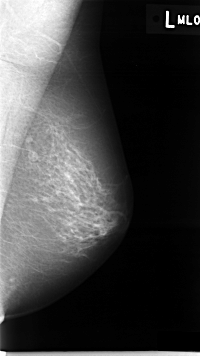

C_0010_1.LEFT_MLO

LEFT_MLO LINES 4616 PIXELS_PER_LINE 2600 BITS_PER_PIXEL 12 RESOLUTION 50 NON_OVERLAY